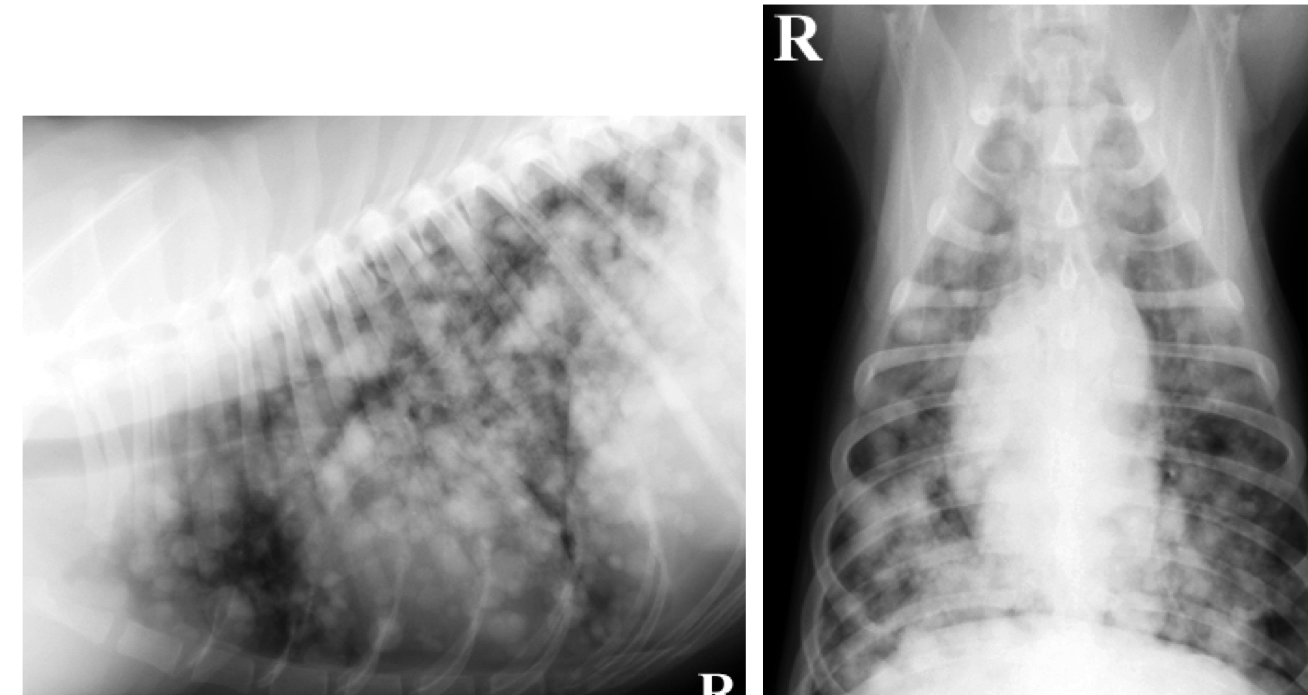

classify distribution

A

Diffuse